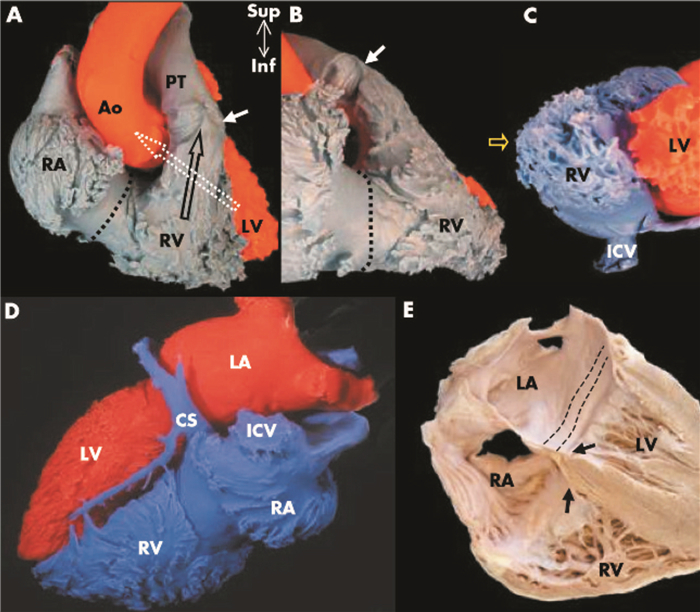

超声心动图通过不同切面显示右心室长轴、左心室短轴和四腔心层面显示右心的结构特点,见图 3。[8]

| 图 3 右心室长轴可以显示右心房、右心室及右心室流出道;左心室短轴显示右心室呈新月形及部分三尖瓣瓣叶;心尖四腔心显示左右心房、左右心室及三尖瓣 |